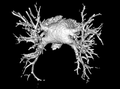

Bronchial anatomy

Bronchial anatomy Bronchi, bronchial tree, and lungs